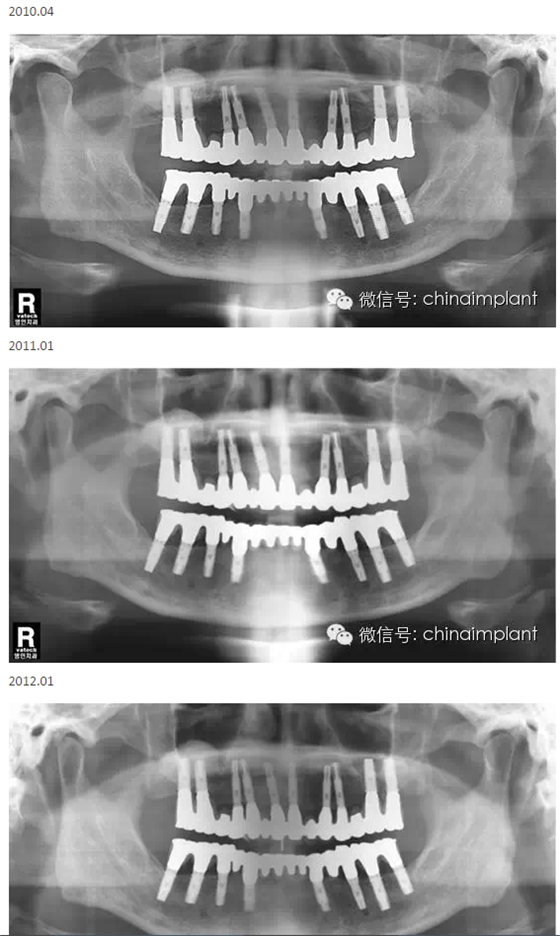

本案例已經(jīng)將近10年了(2005年12月),但是修復(fù)效果個(gè)人認(rèn)為很不錯(cuò),所以拿出來和大家分享。

從修復(fù)全景片上看到牙齒排列非常好

轉(zhuǎn):北京北一